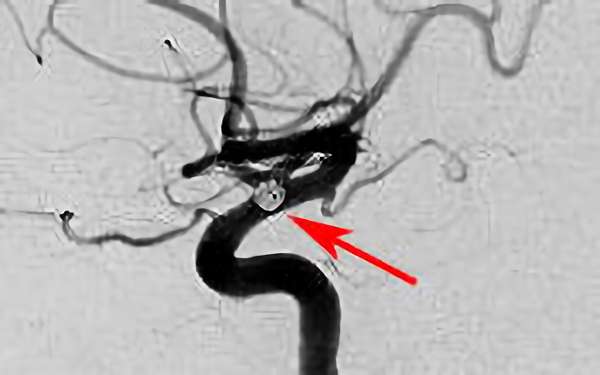

脳動脈瘤(血管内治療)実績一覧 (合計 791 件)

※ 画像をクリックすると拡大表示します。症例No.をクリックすると詳細ページを表示します。